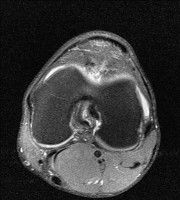

무릎 mri 간단히 봐주실 수 있으시나요 ㅠㅠ

안녕하세요 8년전 십자인대 수술하고 최근 무리한 운동에 무릎 불편감이 생겨서

mri 찍었습니다.

진단결과는 첫 찍은 병원에서 활액막염 이라는 진단을 받았습니다. 혹시 봐주실 수 있으실까요?

올라온 MRI가 단편적이라서 정확한 진단에 어려움이 있지만 십자인대에는 큰 이상이 있지는 않은것 같으며, 무릎관절내 물이 있는 것으로 보아 활액막염의 진단이 맞을 것 같습니다.

하지만 단편적인 영상이기 때문에 촬영병원에서 정확한 판독지 등을 받으시는 것이 좋겠습니다.